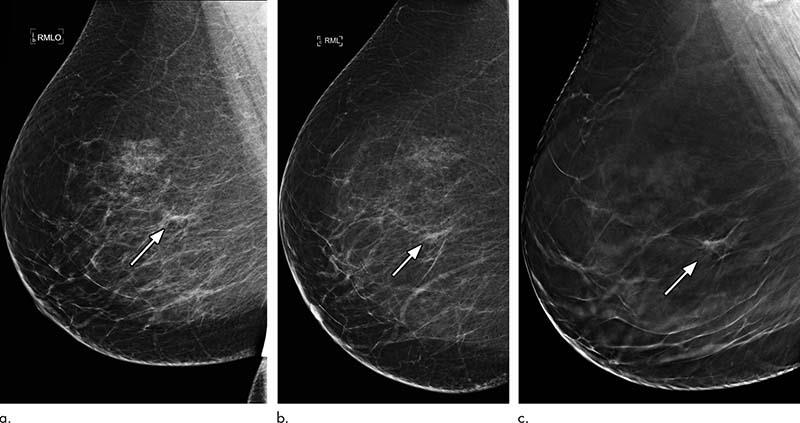

Images in a 46-year-old asymptomatic woman who was recalled for asymmetry in the right breast that was assessed as benign on further diagnostic mammograms and in whom targeted US findings were normal. Full-field digital mammography findings were false negative, and biopsy re¬vealed intermediate ductal carcinoma in situ. (a) Right mediolateral oblique (MLO) and (b) lateral views. (c) Right MLO digital breast tomosynthesis (DBT) image shows an indeterminate spiculated density that was coded R3 indeterminate. Stereotactic-guided DBT biopsy was performed and revealed a papil¬loma with atypia. The patient underwent surgical diagnostic biopsy, which showed a 4-mm intermediate-grade ductal carcinoma in situ.